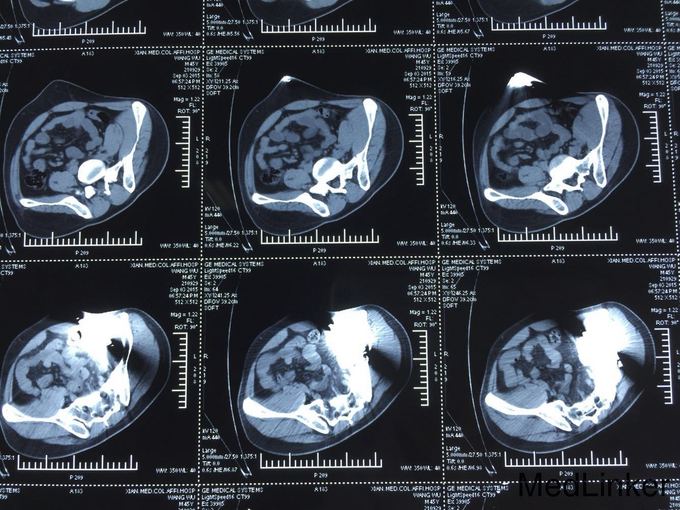

查体:T:36.6℃,P:80次/分,R:19次/分,Bp:130/85mmHg。心肺未见明显异常,腹平坦,无腹壁静脉曲张,腹部柔软,无压痛、反跳痛,腹部无包块,左侧腰髂部近左臀部可见钢筋样异物刺入直达左下腹腹壁皮下,未穿透腹壁皮肤,左臀部皮肤裂伤伴出血,伤口处压痛,肝脾肋下未触及,左下腹压痛,Murphy氏征阴性,移动性浊音阴性,肝脾肾区无叩击痛,肠鸣音未见异常。 辅助检查:全腹部CT检查示:1.盆腔见条状金属致密物,从左臀穿向前下腹部皮下,长约28cm;2.左侧腹膜周围见少许渗出性改变;3.左侧精索肿胀,其内气体影,左侧睾丸肿胀;4.左侧髂骨骨折。

诊断: 左侧腰骶部开放性损伤:左侧腰髂部盲管伤,腹膜后血肿,左侧精索静脉损伤,左侧髂骨骨折。 诊疗过程:入院后积极完善术前检查,无绝对手术禁忌,予以急诊行剖腹探查手术:左下腹乙状结肠外侧部位可见腹膜后血肿形成,初步判断钢筋样异物经左侧骶髂关节部位刺入至左下腹腹膜后部位后再经由壁腹膜外位至左下腹壁,遂决定行腹膜后血肿探查清除手术:于乙状结肠外侧后腹膜血肿部位打开后腹膜并清除积血,探查见左侧髂血管未见外伤性改变,探查见左侧精索静脉断裂伴出血,予以细线结扎,左侧输尿管、左肾、膀胱未见外伤性改变。冲洗腹腔干净,继续探查判断左下腹钢筋样异物均位于腹膜外位且未伤及重要器官,遂经腹壁侧予以拔出,查腹腔无活动性出血,,于左下腹腔术区置橡皮引流管一条经左侧腹壁引出,逐层缝合关闭腹腔,随后行臀部外伤扩创术。术后患者恢复佳,顺利出院。